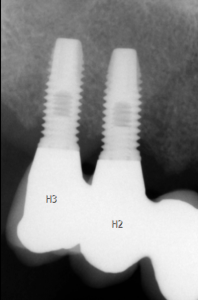

図1 上部構造のない骨結合インプラント

図2 上部構造を有する骨結合インプラントのX線写真